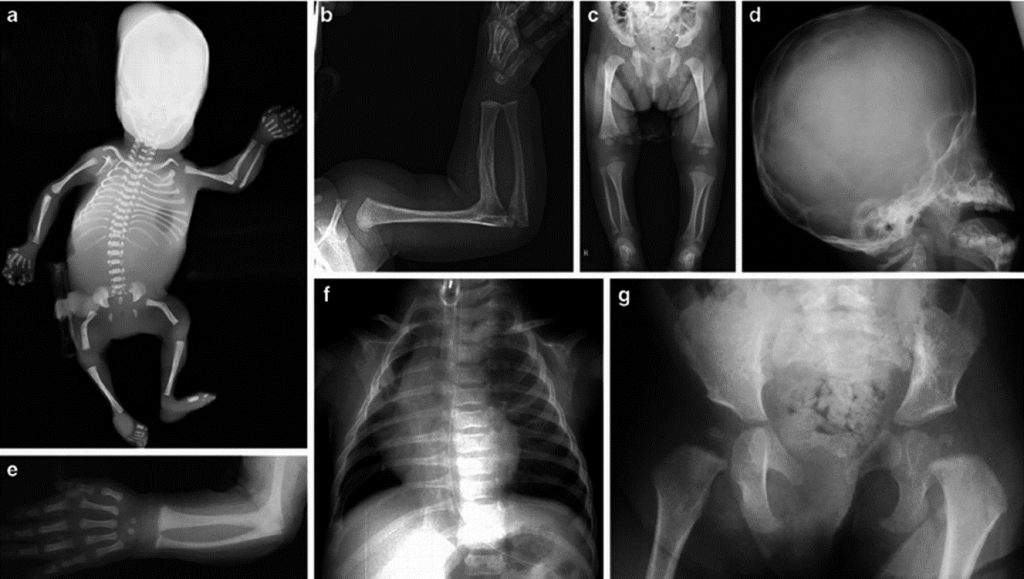

Antley–Bixler fenotipi, özellikle P450 oksidoredüktaz (POR) eksikliği ile ilişkili; kraniofasiyal + iskelet anomalileri ve sıklıkla genital anomalilerle seyreden bir klinik tablodur.

1-Kraniofasiyal; Kraniosinostoz (özellikle koronal), Orta yüz hipoplazisi, Düz / basık burun kökü, Düşük yerleşimli kulaklar

2-İskelet; Radyo-ulnar sinostoz, Uzun kemik anomalileri, Kontraktürler, Femur eğrilikleri

3-Genital / Endokrin; Ambigus genitalya